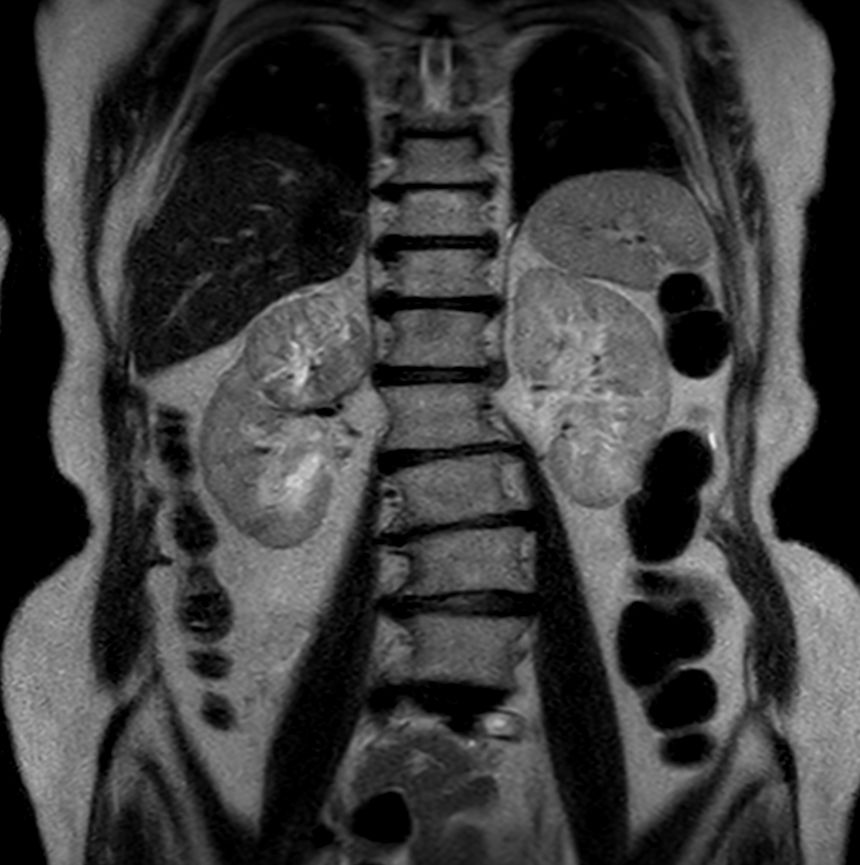

Patient with renal failure. ExamCard includes MultiVane XD to acquire motion-free diagnostic images and 4D FreeBreathing to perform multi-phase contrast-enhanced MRI studies.

T2w TSE - Free Breathing (6 mm)